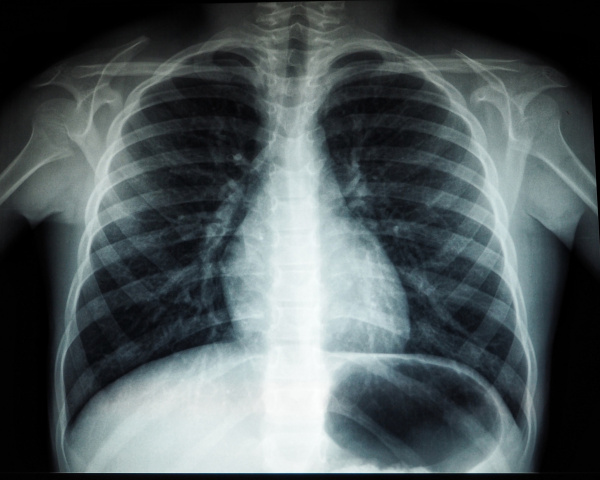

36-летний житель Красноярского района Самарской области стоит на учете в наркологическом диспансере и обязан проходить флюорографию. Однако в добровольном порядке мужчина от прохождения обследования отказывался. Пройти медицинский осмотр в обязательном порядке его заставил суд.

Судебный пристав уведомил мужчину об обязанности пройти флюорографическое обследование, и пояснил, что в противном случае к нему применят меры принудительного характера.